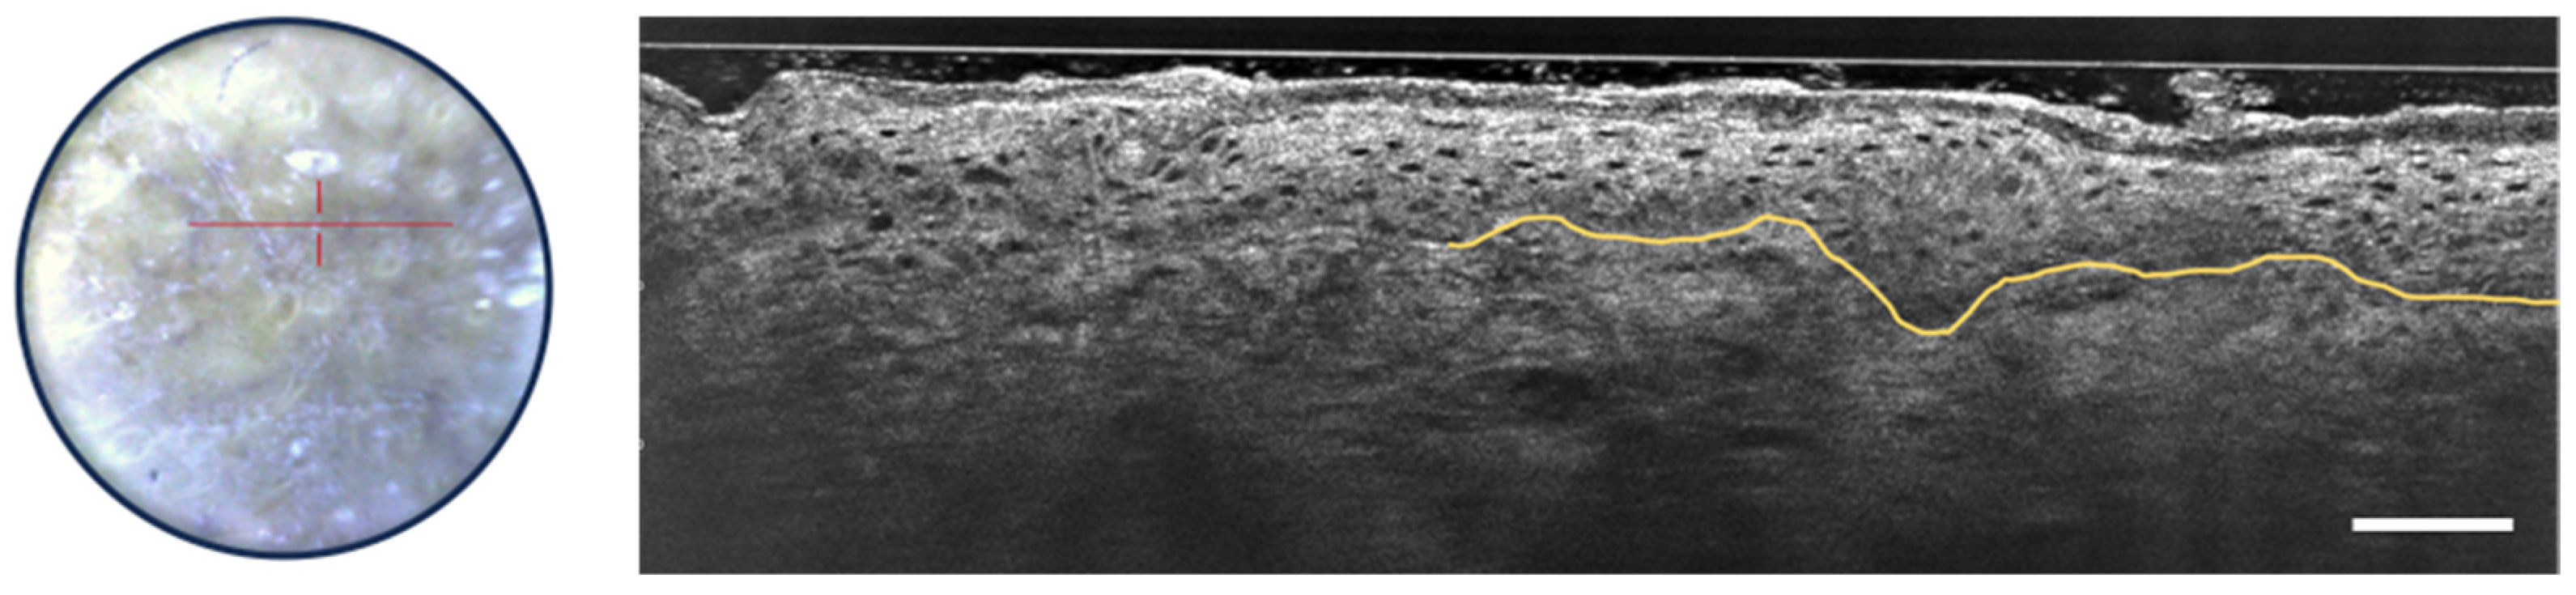

3.1. Melanocytic Skin Tumors

- Schuh, S.; Ruini, C.; Perwein, M.K.E.; Daxenberger, F.; Gust, C.; Sattler, E.C.; Welzel, J. Line-Field Confocal Optical Coherence Tomography: A New Tool for the Differentiation between Nevi and Melanomas? Cancers 2022, 14, 1140. [Google Scholar] [CrossRef] [PubMed]

- Perez-Anker, J.; Puig, S.; Alos, L.; García, A.; Alejo, B.; Cinotti, E.; Cano, C.O.; Tognetti, L.; Lenoir, C.; Monnier, J.; et al. Morphological evaluation of melanocytic lesions with three-dimensional line-field confocal optical coherence tomography: Correlation with histopathology and reflectance confocal microscopy. A pilot study. Clin. Exp. Dermatol. 2022, 47, 2222–2233. [Google Scholar] [CrossRef]

- Lenoir, C.; Perez-Anker, J.; Diet, G.; Tognetti, L.; Cinotti, E.; Trépant, A.; Rubegni, P.; Puig, S.; Perrot, J.; Malvehy, J.; et al. Line-field confocal optical coherence tomography of benign dermal melanocytic proliferations: A case series. J. Eur. Acad. Dermatol. Venereol. 2021, 35, E399–E401. [Google Scholar] [CrossRef]